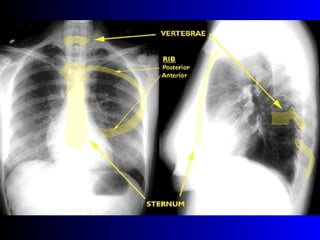

Este documento describe la técnica para realizar una telerradiografía de tórax normal e identifica las estructuras visibles en la imagen, incluyendo los huesos, vasos sanguíneos, grasa, tejido subcutáneo, pulmones y mediastino. Explica que es importante centrar la imagen en los ápices pulmonares, senos costodiafragmáticos e inspiración profunda para una visión clara de las estructuras.